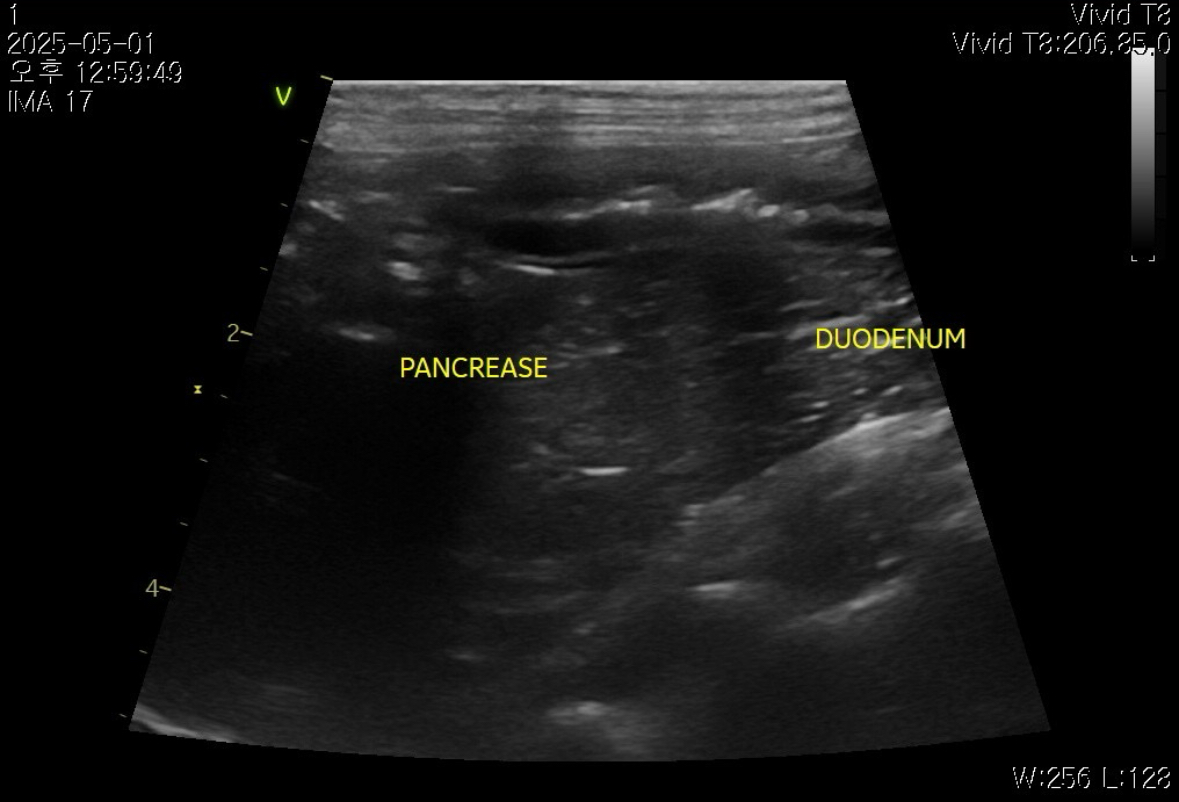

[초음파]